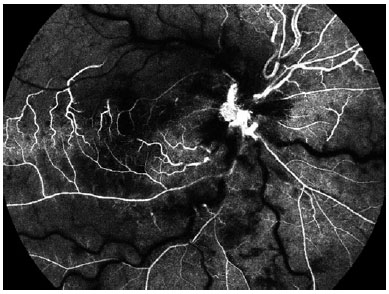

An 11-year-old boy presented to our department with blurry vision in his right eye since he woke up. He denied any ocular pain; however, his parents reported a weight loss over the previous 6 months and persistent cough and mild headache in the previous week. The patient had a history of vernal conjunctivitis and was prescribed topical cyclosporine and corticosteroids. The best-corrected visual acuity (BCVA) was counting fingers (CF), and a relative afferent pupillary defect of the affected eye was observed. Intraocular pressure was 11 mm Hg. Biomicroscopy exam was normal. Right eye fundoscopy revealed optic disc edema, tortuous dilated retinal veins, retinal hemorrhages, and macular edema (ME). Color fundus photography, spectral-domain optical coherence tomography (SD-OCT), and fluorescein angiography (FA) were performed. FA confirmed the diagnosis of CRVO (Figure 1). SD-OCT showed cystoid ME (Figure 2). Therefore, the patient was admitted for further investigation.

02-fig01.jpg)